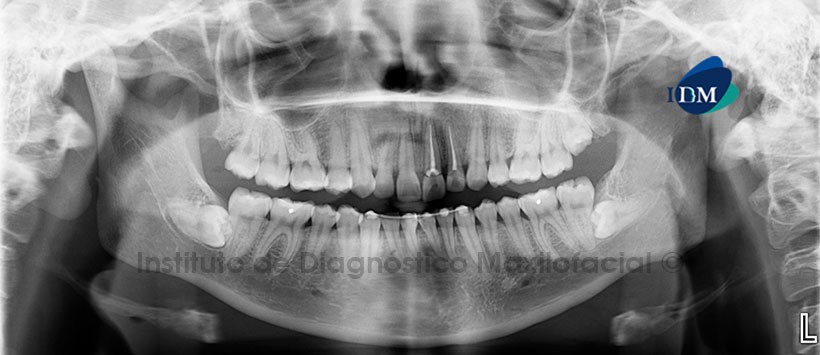

A la evaluación de la radiografía panorámica, se aprecia material de obturación de conductos en las piezas 2.1 y 2.2, en pieza 1.1 se observa espacio periodontal engrosado a nivel apical. Piezas 1.4 y 2.4 ausentes. La pieza 1.5 presenta obliteración parcial de cámara y conducto radicular. Alambre de fijación en el sector ántero inferior. (Figura 1).